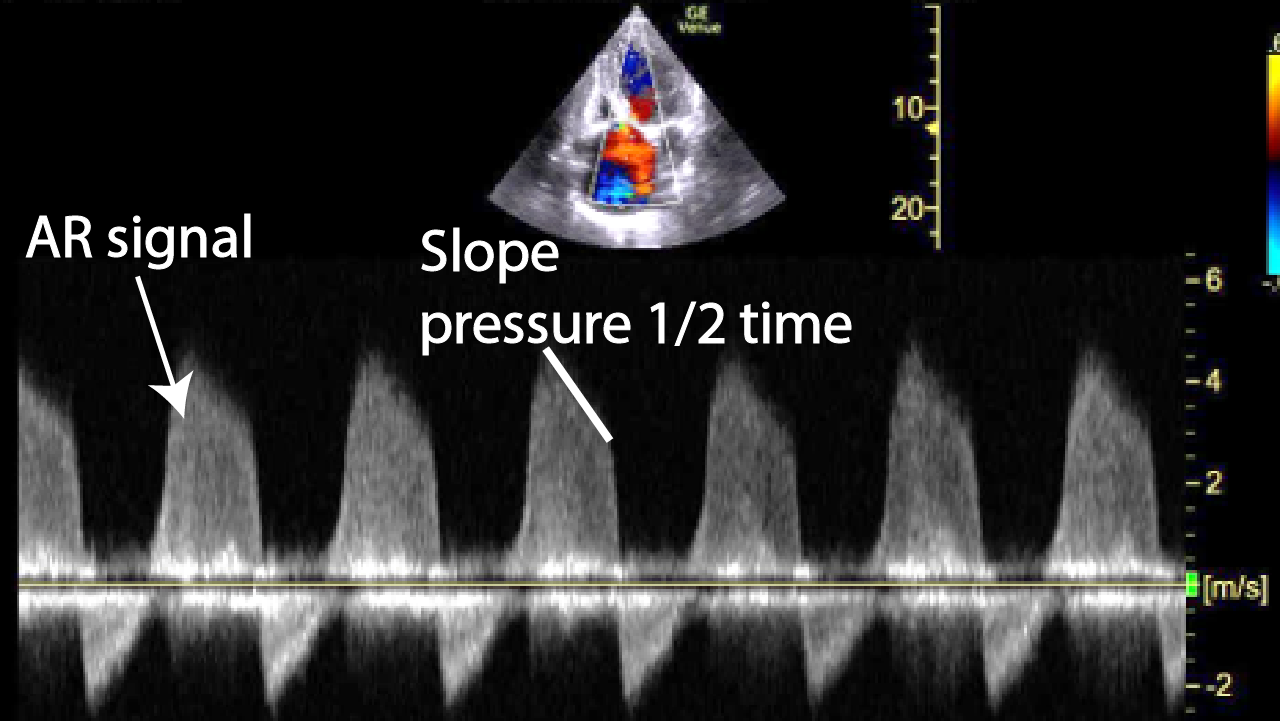

How To Measure Pressure Half-Time Aortic Regurgitation . The etiology of the diastolic doppler flow. The drop in the pressure gradient is gradual in patients with mild aortic obtain a pwd or a cwd of the aortic valve. echocardiography has become the standard method for evaluating aortic regurgitation severity. Emphasis on identification of etiology/mechanism of regurgitation. picture demonstrates measurement of pressure half time of. pht measurement by doppler echocardiography is useful in assessing the severity of aortic regurgitation. the following is obtained: Indicated by the arrow is: pressure half time (pht) is defined as the time it takes for the initial maximal pressure gradient across the aortic valve to fall by 50% during diastole. The flow profile of the aortic valve, in aortic regurgitation will show a diastolic flow. Other methods such as cardiac.

How To Measure Pressure Half-Time Aortic Regurgitation The flow profile of the aortic valve, in aortic regurgitation will show a diastolic flow. pressure half time (pht) is defined as the time it takes for the initial maximal pressure gradient across the aortic valve to fall by 50% during diastole. The etiology of the diastolic doppler flow. pht measurement by doppler echocardiography is useful in assessing the severity of aortic regurgitation. Other methods such as cardiac. obtain a pwd or a cwd of the aortic valve. picture demonstrates measurement of pressure half time of. Emphasis on identification of etiology/mechanism of regurgitation. The drop in the pressure gradient is gradual in patients with mild aortic echocardiography has become the standard method for evaluating aortic regurgitation severity. Indicated by the arrow is: The flow profile of the aortic valve, in aortic regurgitation will show a diastolic flow. the following is obtained:

PPT Aortic Regurgitation PowerPoint Presentation, free download ID How To Measure Pressure Half-Time Aortic Regurgitation echocardiography has become the standard method for evaluating aortic regurgitation severity. pht measurement by doppler echocardiography is useful in assessing the severity of aortic regurgitation. pressure half time (pht) is defined as the time it takes for the initial maximal pressure gradient across the aortic valve to fall by 50% during diastole. Other methods such as cardiac.. How To Measure Pressure Half-Time Aortic Regurgitation.